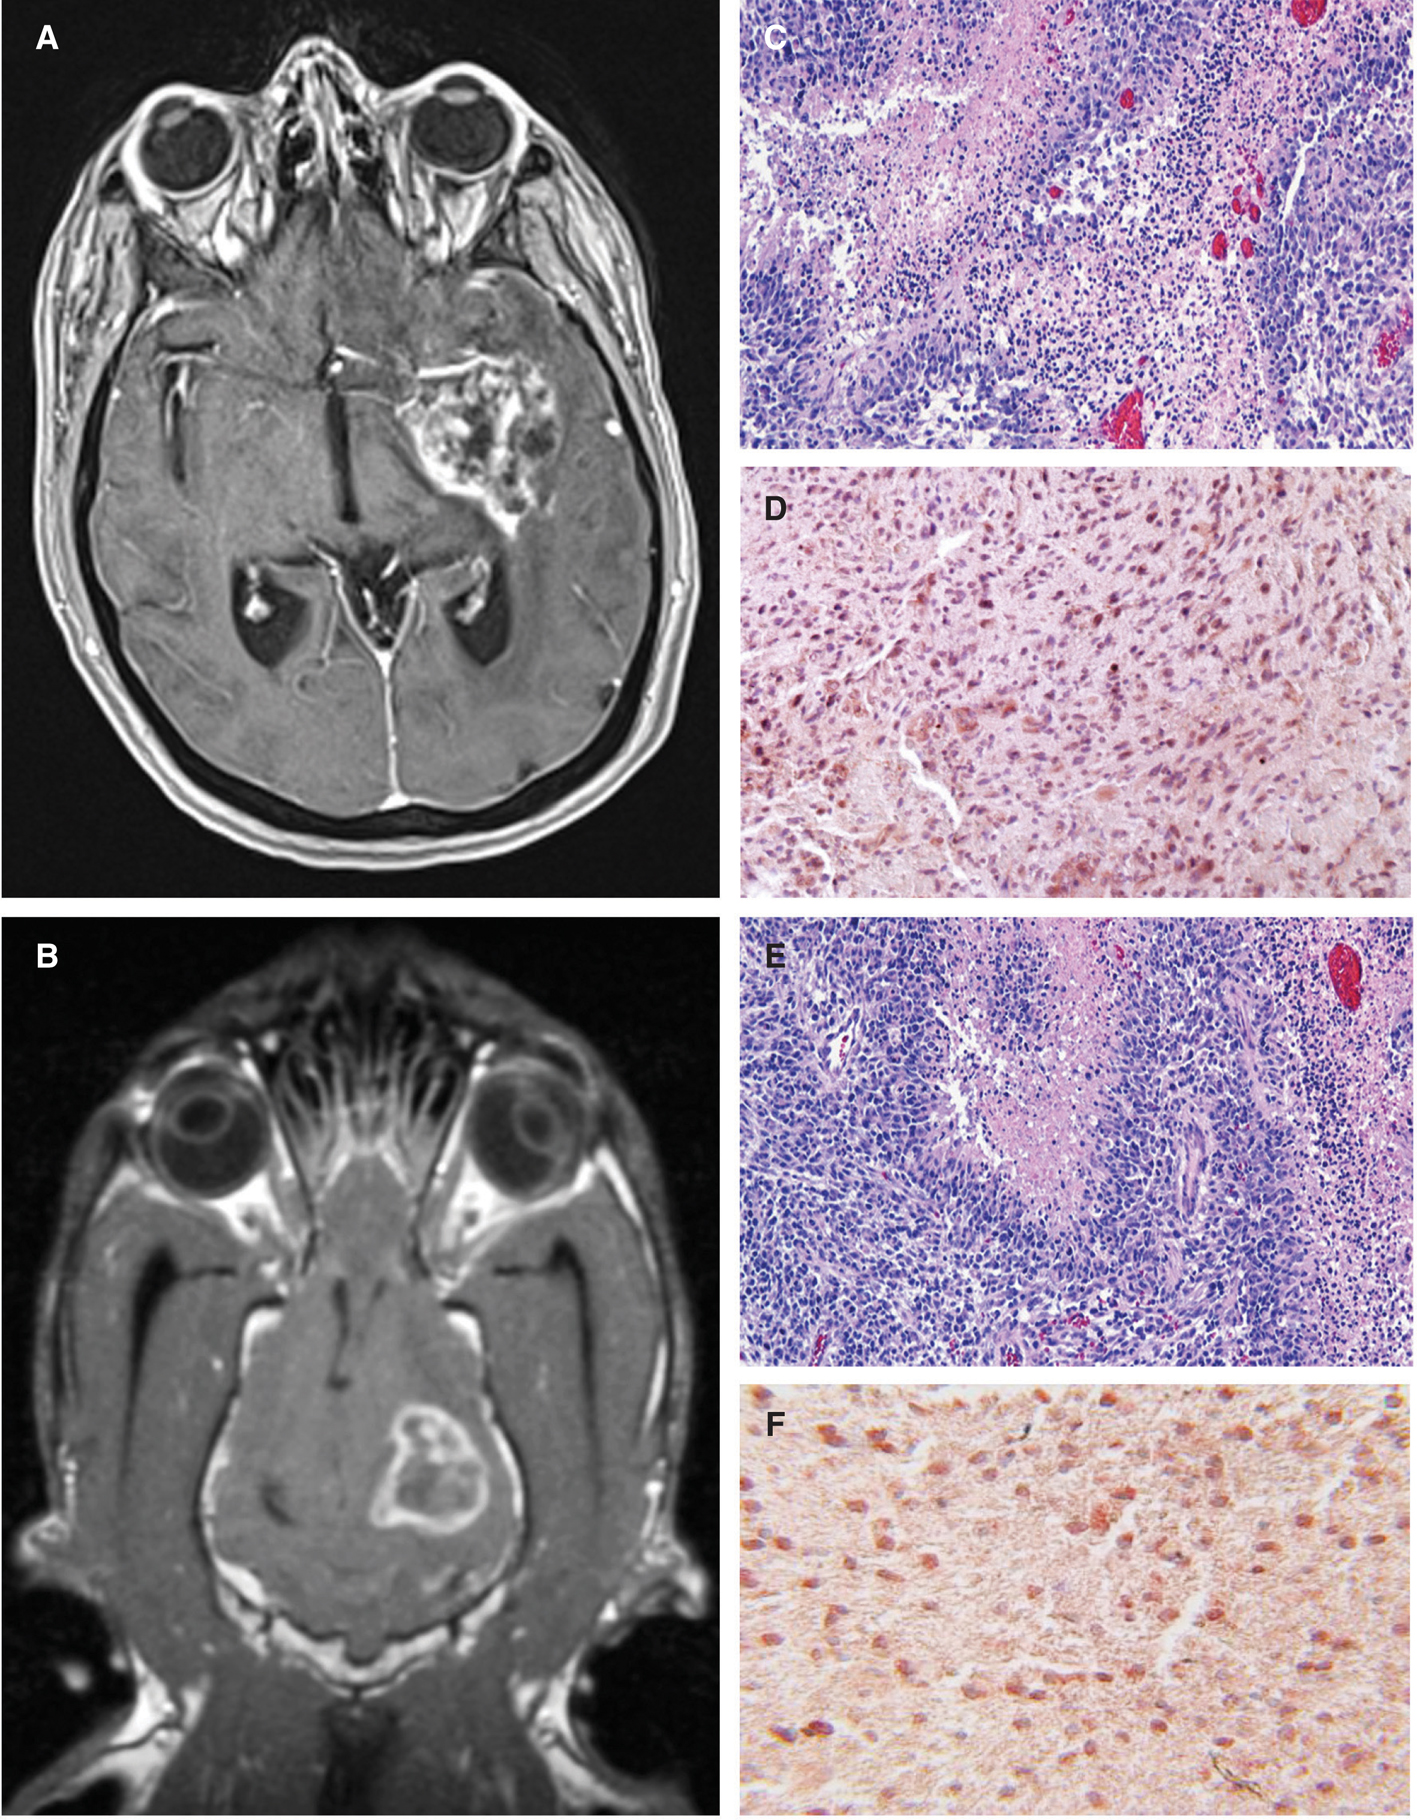

The histopathological and diagnostic imaging features of canine gliomas (Figure 1) are also remarkable similar to their human counterparts (3135). These shared morphologic features facilitate comparative classification and grading of tumors using World Health Organization criteria (36) and performing objective imaging–based therapeutic response assessments using the Response Assessment in Neuro-Oncology (RANO) system criteria (28, 37). However, the frequency of glioma subtypes encountered in dogs differs from that seen in humans (Table 1), with oligodendrogliomas accounting for a significantly higher proportion of all canine gliomas compared to humans (1921, 23, 37).

Fig 1

Figure 1 Comparative morphological and immunophenotypical features of human and canine glioblastoma (GBM). Post-contrast T1-weighted magnetic resonance images from a human (A) and dog (B) demonstrating ring-enhancing cerebral GBM. Classic microscopic features of hypercellularity and pseudopalisading necrosis in a human (C) and canine (E) GBM (H&E stain, bar = 150 μm). GBM from both species demonstrate intense immunoreactvity to IL-13RA2 (D, F).

Building upon these advancements and cognizant of the lessons learned from prior CED clinical trials, we are investigating the use of CED to deliver high-molecular weight-targeted therapeutics to canine gliomas. Given the potential efficacy of first generation of IL-13RA2 conjugated pseudomonal exotoxins in human GBM (67), and common overexpression of IL-13RA2 and EphA2 in canine and human gliomas (Figure 1), potent IL-13 and ephrin-A1-based cytotoxins containing modified Pseudomonas exotoxin A or Diphtheria toxin targeted to IL-13RA2 and EphA2 receptors were generated, respectively (47, 48, 68, 69). We are actively conducting a clinical trial in dogs with gliomas to evaluate the tolerability and preliminary efficacy of this targeted bacterial cytotoxic cocktail administered by delivered using MRI-monitored CED.